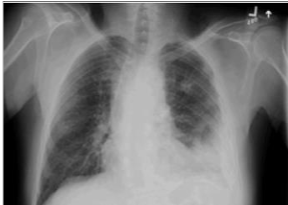

Observe a radiografia de tórax a seguir.

Enunciado 3185076-1

Disponível em: https://bestpractice.bmj.com/topics/pt-br/287. Acesso em: 22 set. 2022.

A radiografia de tórax é utilizada como um instrumento de rápida avaliação das anormalidades no tórax. A imagem é de um paciente de 64 anos que chegou ao pronto-socorro com taquipneia e dessaturação. No caso da radiografia apresentada, ela evidencia